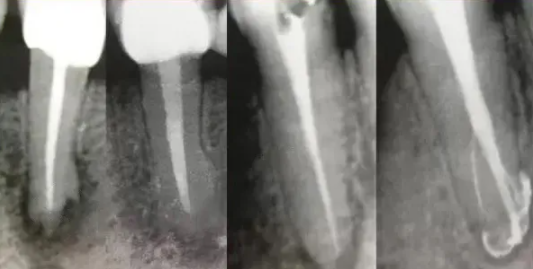

5、预备到多少号结束

根管预备理想的情况应该预备到多大锥度,多少号,预备后根管空间是金字塔还是埃菲尔铁塔。专家经过离体牙根尖切片研究发现根尖狭窄部远比想象的要大,如果根管预备太小就会残留感染物,根管的部分空间就不会预备到,残留的感染物就会造成治疗效果达不到预期目标。只有做到了充分的预备,尽可能的多冲洗才会有好的结果。

根管治疗要做到看清楚,去干净,充恰满,封严密,就会达到期望的结果。多年前的病例只充填了冠1/3可以理解、可以接受;但今天我们有先进的设备和材料,就要充填出大锥度高密度的完美结果。理念决定技术,标准决定技术的提高和进步。